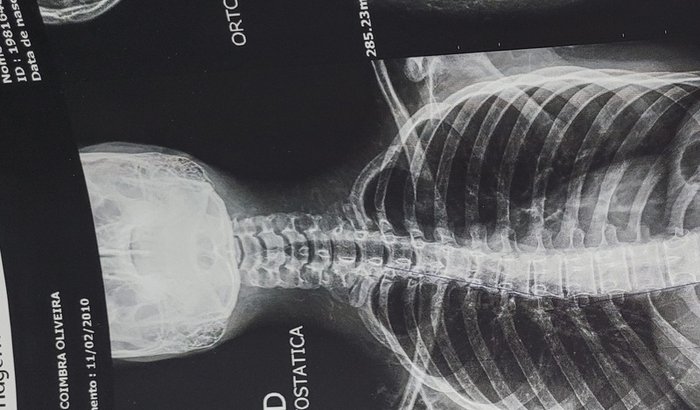

Olá! Meu nome é Rayka tenho 12 anos fui diagnosticada com ESCOLIOSE IDIOPATICA desalinhamento na coluna que precisa ser tratado pois pode atingir estruturas ósseas causando dores musculares, desconforto podendo comprometer a respiração e órgãos vitais.Sinto muitas dores nas costas após fazer exames foi me indicado usar colete 3D para escoliose até completar a maturidade óssea (parar de crescer)

Na medida que vou crescendo se não for tratado a coluna vertebral vai sofrendo alterações e entortando cada vez mais.O colete 3D sob medida tem o custo de R$4.500,00 o qual preciso começar a usar o mais breve possível para iniciar o tratamento.(Meus pais no momento não tem condições de arcar com esse valor)Por isso venho pedir ajuda de cada um que puder contribuir para o meu tratamento.Eu e minha família agradecemos desde já todo apoio possível. Que Deus possa retribuir em dobro cada um de vocês.